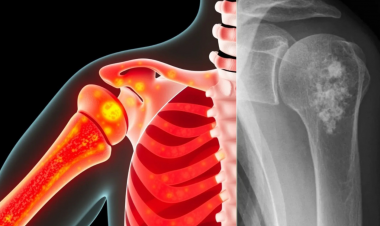

核医学影像新突破:PET参数Dmax为黑色素瘤免疫治疗提供精准预后依据